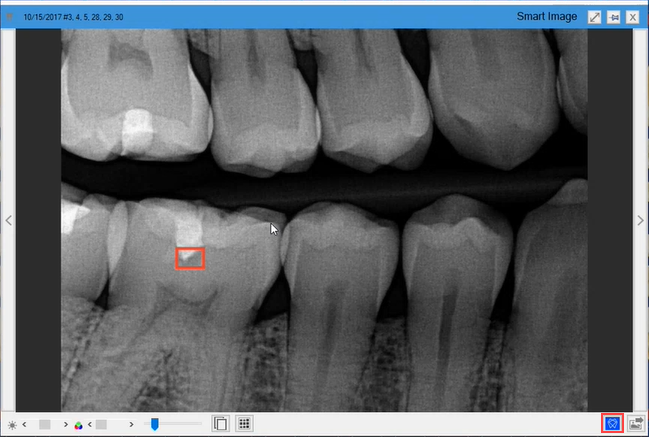

The Diagnostic Viewer appears, the image processes, and any caries Dentrix Detect AI found are outlined in red.

3. To view the details of the analysis or to hide the results, click the VideaHealth AI button.